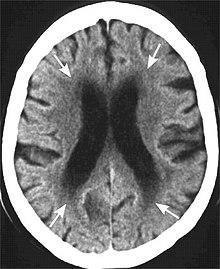

MRI image: Leukoaraiosis in a 90-year-old patient with cerebral atrophy.

Head CT showing periventricular white matter lesions.

Leukoaraiosis is a particular abnormal change in appearance of white matter near the lateral ventricles. It is often seen in aged individuals, but sometimes in young adults.[1][2] On MRI, leukoaraiosis changes appear as white matter hyperintensities (WMHs).[3][4] On CT scans, leukoaraiosis appears as hypodense periventricular white-matter lesions.[5]